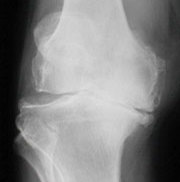

Slidgigt er den mest udbredte ledsygdom, der rammer stort set alle med alderen. Otte ud af ti har slidgigt, når de har passeret de 50 år. Slidgigt opstår, når brusken mellem knoglerne eftrhånden nedbrydes, og det er den mest almindelige årsag til, at der er behov for at indsætte en knæprotese.

De første symptomer er typisk smerter ved igangsætning, ømhed efter belastning og hævelse. Ved svær slidgigt opstår der ofte hvilesmerter, nedsat bevægelighed og måske fejlstilling i ledde.

Hvis du kun har slidgigt i det ene ledkammer - hyppigst på indersiden af knæet, anbelafer vi ofte en delprotese (Uniknæ). Dette er tilfældet for ca. 30 - 50% af alle patienter med slidgigt i knæet.